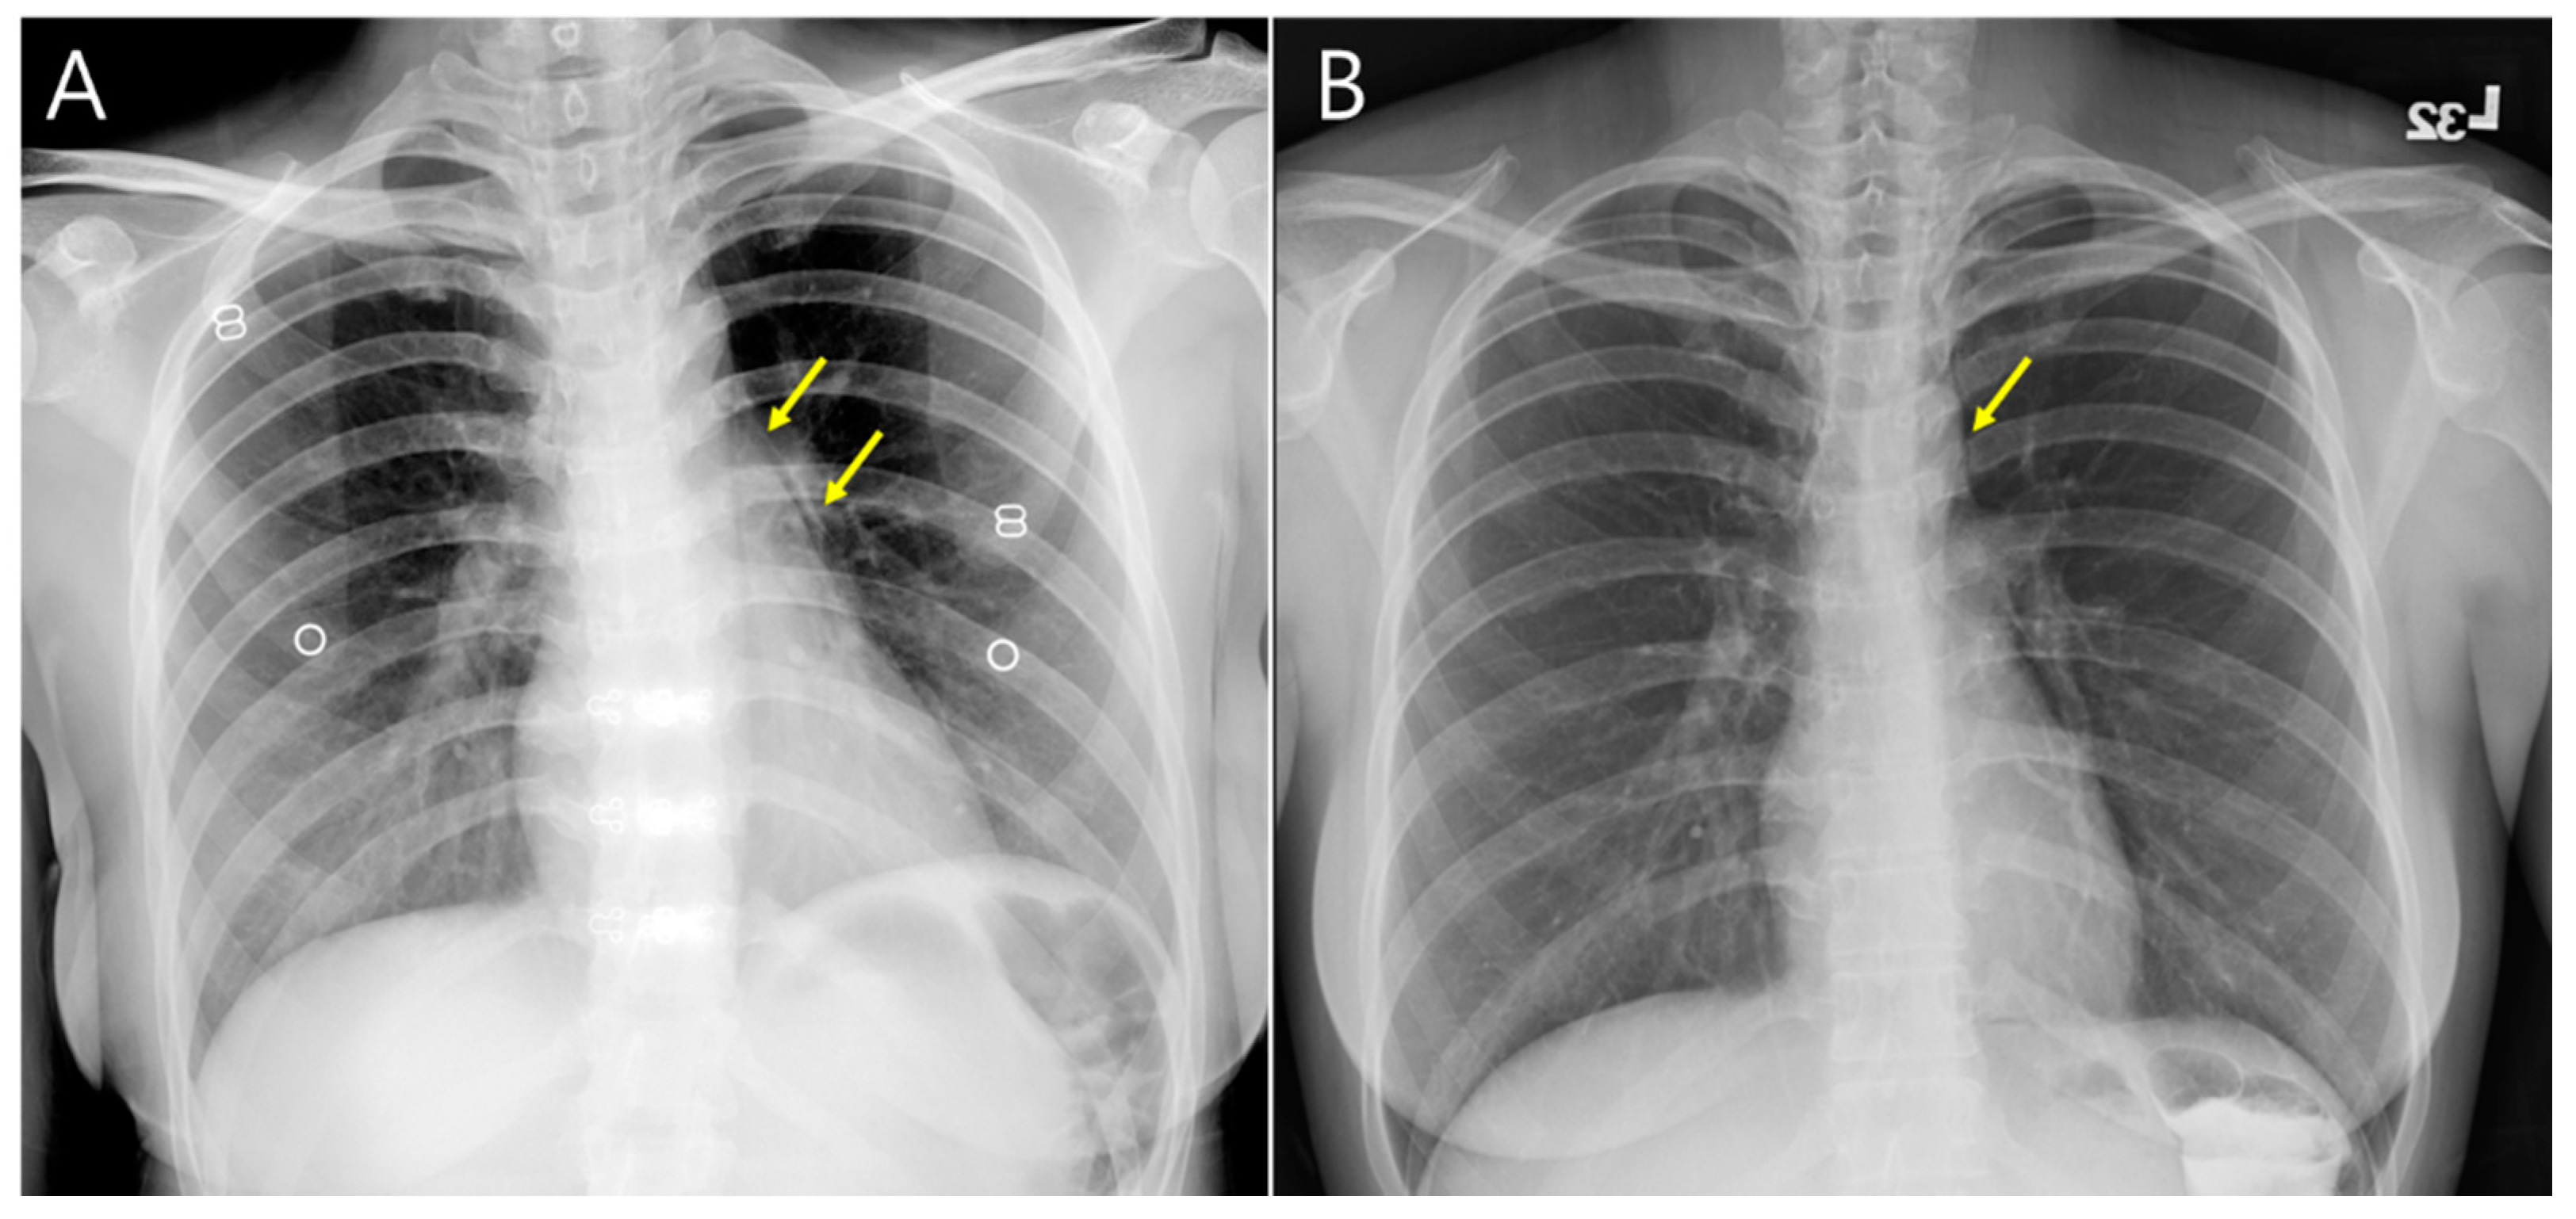

Figure 5.

Sequential chest X-ray (A) on admission day and (B) discharge day showed improvement of pneumomediastinum (yellow arrow). There was no pleural effusion and pericardial effusion.